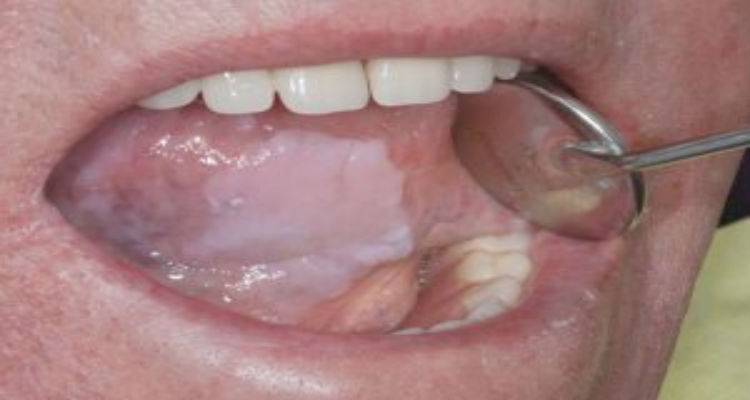

Τι είναι η λευκοπλακία;

Είναι μια προκαρκινική βλάβη που εμφανίζεται στο βλεννογόνο του στόματος με τη μορφή λευκής πλάκας. Η πλάκα αυτή είναι προσκολλημένη πάνω στον βλεννογόνο του στόματος. Μελέτες που έχουν γίνει έχουν δείξει ότι το 85-90% των πασχόντων είναι μανιώδεις καπνιστές (ένα έως τρία πακέτα την ημέρα) τουλάχιστον μια δεκαετία και με ελλιπή στοματική υγιεινή.

Η λευκοπλακία είναι προκαρκινική κατάσταση, γεγονός που σημαίνει ότι αν δεν αντιμετωπιστεί εγκαίρως υπάρχει κίνδυνος να εξελιχθεί σε καρκίνο. Οι πιθανότητες διαφέρουν ανάλογα με το σημείο του στόματος όπου αναπτύσσεται η βλάβη. Έτσι έχουμε περιοχές «υψηλού κινδύνου», όπως το έδαφος του στόματος και η γλώσσα με πιθανότητες κακοήθους εξαλλαγής 15-20% και «χαμηλού κινδύνου», όπως τα ούλα με πιθανότητες 5-6%.